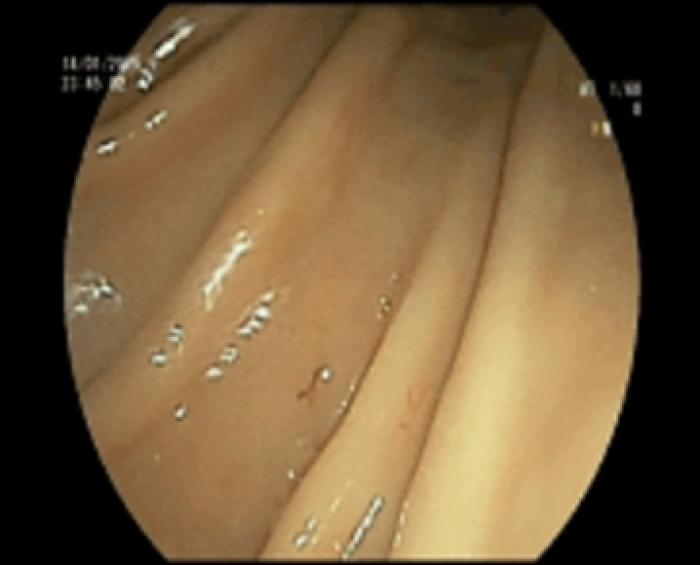

- Atrofia severa de vellosidades duodenales (Figura 4)

Después de 15 días se realiza esofago-gastro-duodenoscopia, colonoscopia e ileoscopia para realizar biopsias, obteniendo los siguientes resultados:

- Gastritis congestiva ligera (Figura 12)

- Duodenitis congestiva y erosiva moderada (Figura 13)